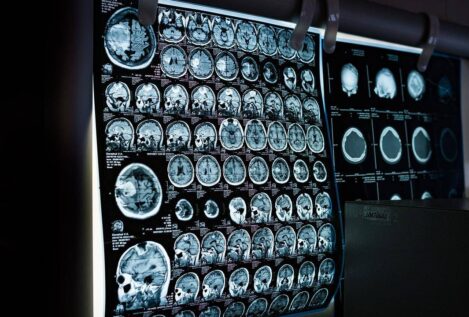

Estudios recientes muestran que los algoritmos de aprendizaje automático (AAA) son capaces de predecir el sexo a partir de escáneres del cerebro

Los recientes resultados de unas decenas de estudios científicos que muestran que los algoritmos de aprendizaje automático (AAA) son capaces de predecir el sexo a partir de imágenes de escáneres cerebrales.

Esta segunda posición parece verse avalada por los recientes resultados de unas decenas de estudios científicos que muestran que los algoritmos de aprendizaje automático (AAA) son capaces de predecir el sexo a partir de imágenes de escáneres cerebrales. ¡Y que lo hacen con un porcentaje de acierto que puede superar el 90%! ¿Es esta la prueba definitiva de que existen dos tipos de cerebros?